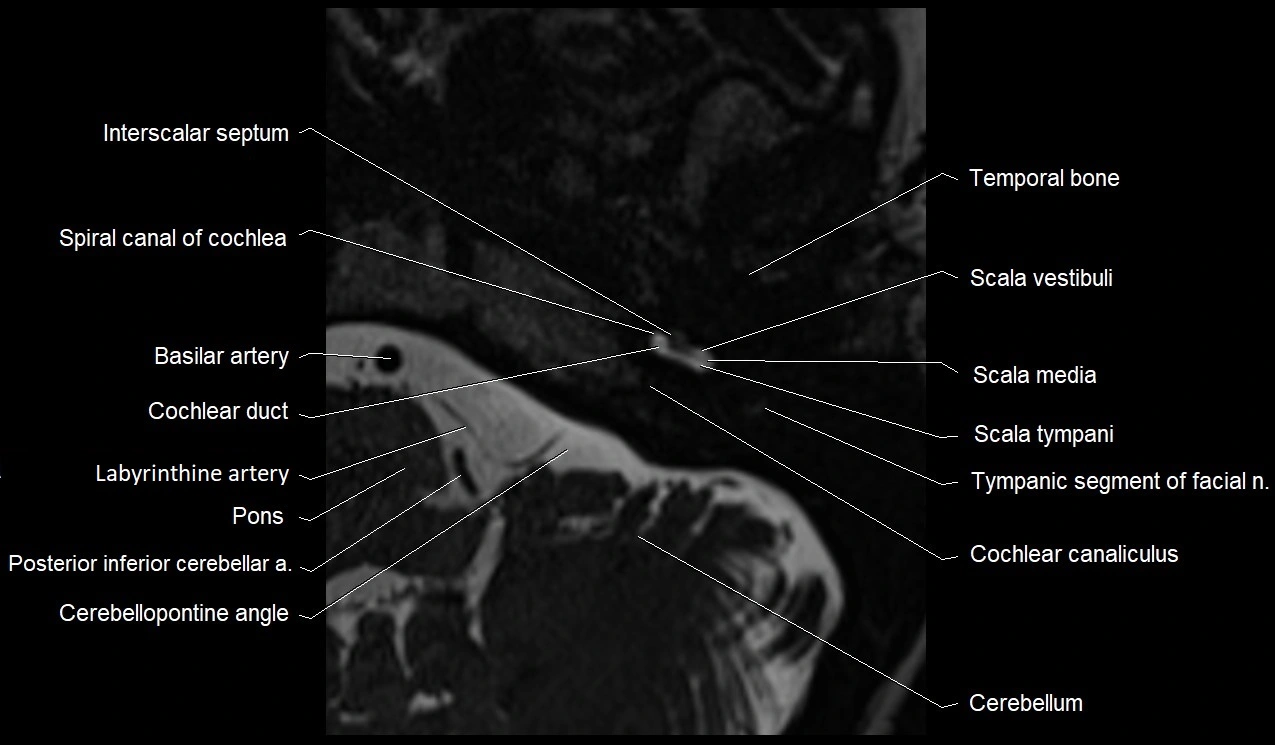

MRI Appearance

• The abducens nerve is a small, thin, linear structure

• Best visualized on high-resolution T2-weighted 3D MRI sequences (e.g., FIESTA or CISS)

• Seen as a hypointense (dark) line running from the brainstem at the pontomedullary junction, traversing the prepontine cistern, and entering Dorello’s canal under the petrosphenoidal ligament, then into the cavernous sinus, and finally the orbit

• May be challenging to visualize in standard MRI due to its small size

• Pathology may be inferred by absence, displacement, or enhancement of the nerve